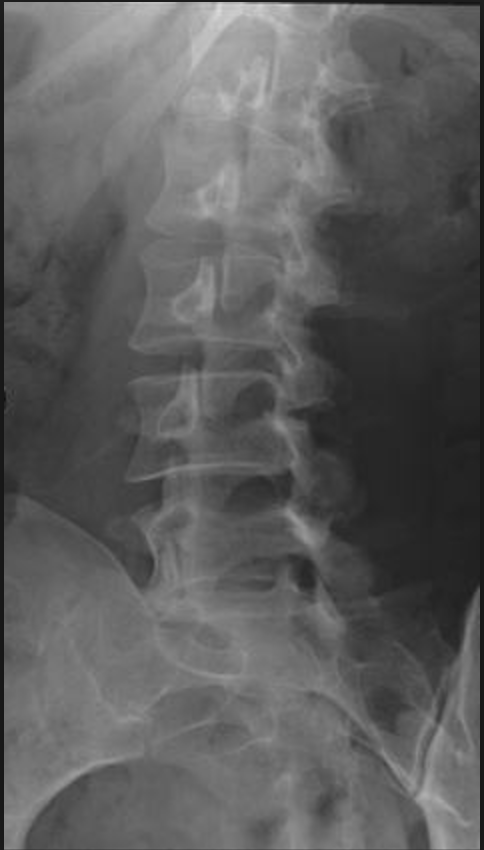

What is this view in the lumbars? What views are missing?

AP (tilt 15 degree SIJ)

MISSING

Lateral

Oblique R & L

L5/S1 spot (AP and Lat)